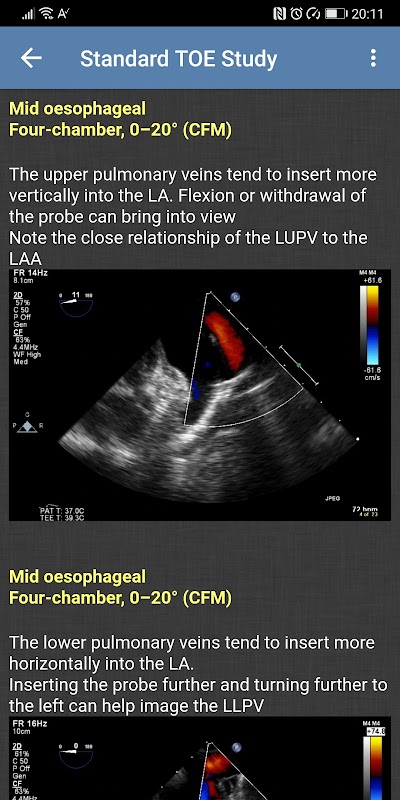

- 标准 TOE 学习